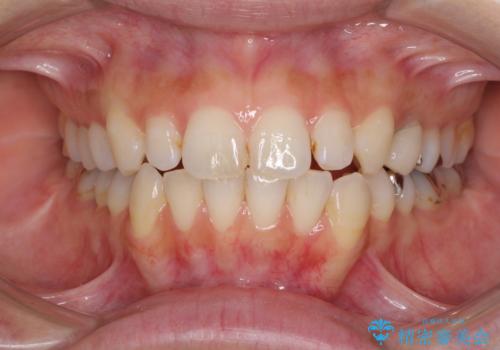

- 前歯のデコボコと矮小歯、更には痛みを感じる奥歯のむし歯を気にして来院された患者様です。

奥歯には根管治療が必要な歯があり、上顎側切歯は左右ともに矮小歯でした。

上下前歯のデコボコはワイヤーでもインビザラインでも対応可能でしたが、補綴治療が多く必要となることから、インビザラインでの矯正治療を行いながら、並行して補綴治療を行うこととしました。

まずは根管治療を行った上で矯正治療用の仮歯を装着し、矯正治療後半に補綴治療を並行して行うこととしました。